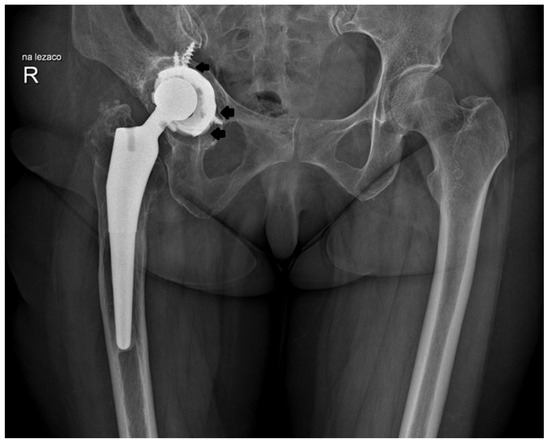

2.2. Design of the L-Cup Acetabular Component

2.4. Acetabular Implantation